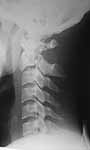

The cervical spine x-ray done on traction in neutral, extension and flexion. Images attached. Request comments.

txn extension

txn neutral

txn flexion

I was disappointed that there was not even one comment after the cervical spine dynamic views were presented. Though there is instability, the CT picture showed that the body of C2 was totally comminuted and hence a decision to keep the patient in Halo was taken by my colleague in charge of the spine unit. After the consolidation of the body of C2 if required he will go through a formal C2-3 fusion.